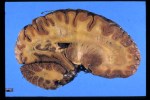

The study suggests that over-activation of two brain areas (Cingulate gyrus and thalamus) lead to “hypervigilance toward emotional stimuli”. In other words the youth could not stop themselves from focusing on negative emotional ideas – this despite an increased activation of the dorsolateral prefrontal cortex (an area of the brain responsible for logical control of emotion).